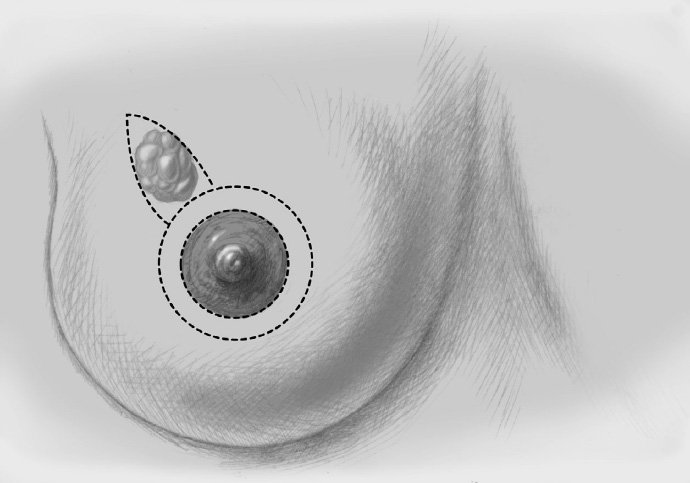

The basic decision on whether to use a complex oncoplastic technique is made when the skin is marked preoperatively, with the patient standing or sitting upright. Many surgeons successfully combine the B-plasty incision with periareolar de-epithelialization and excision of a straight or curved ellipse of peripheral skin (Chapter 1.3). When marking the periareolar deepithelialization pattern, an eccentric incision may be necessary to adjust the repositioning of the nipple–areola complex to the anticipated volume displacement.

The periareolar skin is de-epithelialized. Here, too, there are various options. A strip of the most superficial skin layer can be excised with dissecting scissors applied flat or with a scalpel. It is important not to leave behind any surface containing squamous epithelium, but on the other hand the dermis and the important vascular layer beneath it must not be injured. The purpose of periareolar de-epithelialization is to recenter the nipple–areola complex and also to tailor excess skin to the new breast shape following extensive tumor resection.

Segmental excision of the area containing the tumor with resection margins as wide as possible to meet oncological criteria. Oncoplastic techniques should be used to achieve maximal oncological safety and avoid subsequent further resection.

To cover the defect, the glandular lobes are mobilized from the adjacent parenchyma after subcutaneous dissection. The principle of intramammary lobe creation is to mobilize large parts of the breast (> 25%) either relative to the skin or relative to the pectoralis muscle. This “liberation” of the breast from one of its two planes of fixation allows adequate dissection and rotation of sufficient breast tissue. The Y-flap and rotation flap shown in Chapter 3.2.1 are examples of intramammary dissection.